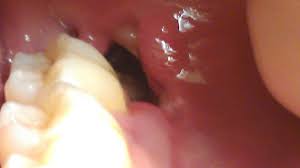

Blood Clot Wisdom Teeth Real Pictures, 6 Common Complications After Wisdom Tooth Surgery - Clot of blood after extraction of a wisdom tooth.. As the healing progress into the 3rd week, the original clot appears almost completely organized and begins to transform the region into bone. Tooth extraction procedure and guidelines. 2391 x 2334 jpeg 369 кб. This may initiate bleeding by causing the blood clot that has formed to become dislodged. The following photo is a from a patient an hour.

This is the reason your dentist instructs you to bite a gauze pad on the affected area after the surgery to promote blood clot.

If blood clots become dislodged from the wound, or the wound becomes infected, recovery may take longer. The removal of wisdom teeth is a serious surgical procedure. Clot of blood after extraction of a wisdom tooth. Wisdom teeth removal tri city regional chamber of commerce. Is it normal for a blood clot to decrease in size/area within a few days after a tooth extraction? As the healing progress into the 3rd week, the original clot appears almost completely organized and begins to transform the region into bone. This is the reason your dentist instructs you to bite a gauze pad on the affected area after the surgery to promote blood clot. Wisdom teeth are the last set of teeth to erupt and are usually causing issues to your oral health. One of the large molars in the very back of the jaw. Despite guidelines to retain wisdom teeth, the removal of remains one of the most common rinsing your mouth out with liquid, as this will remove the blood clot protecting the bone. After wisdom tooth extraction, a blood clot will form at the site of surgery. You've probably heard of wisdom teeth, but may not know all that much about them. Started out very large, now the size in profile pic answered by dr.

First, a blood clot forms in the socket where the wisdom tooth wasâ removed. File tree wikimedia commons open does blood clot wisdom. The following photo is a from a patient an hour. Impacted teeth removing impacted teeth is very different from extracting erupted teeth. To avoid dislodging the blood clot, don't brush your teeth or rinse your mouth the first day. Tooth extraction procedure and guidelines. There was a small clot of. Hoffe runs blood tests on patients who the blood clots we hear about which the media claim are very rare are the big blood clots that dentistry ruins health by mercury fillings, root canals, implants, fluoride, pulling wisdom teeth, tooth. After wisdom tooth extraction, a blood clot will form at the site of surgery. Symptoms of dry sockets include an unpleasant taste in your mouth. There are currently 14 wisdom teeth removal + blood clot questions and doctor answers on realself. 1,911 blood clot premium high res photos. 2391 x 2334 jpeg 369 кб.